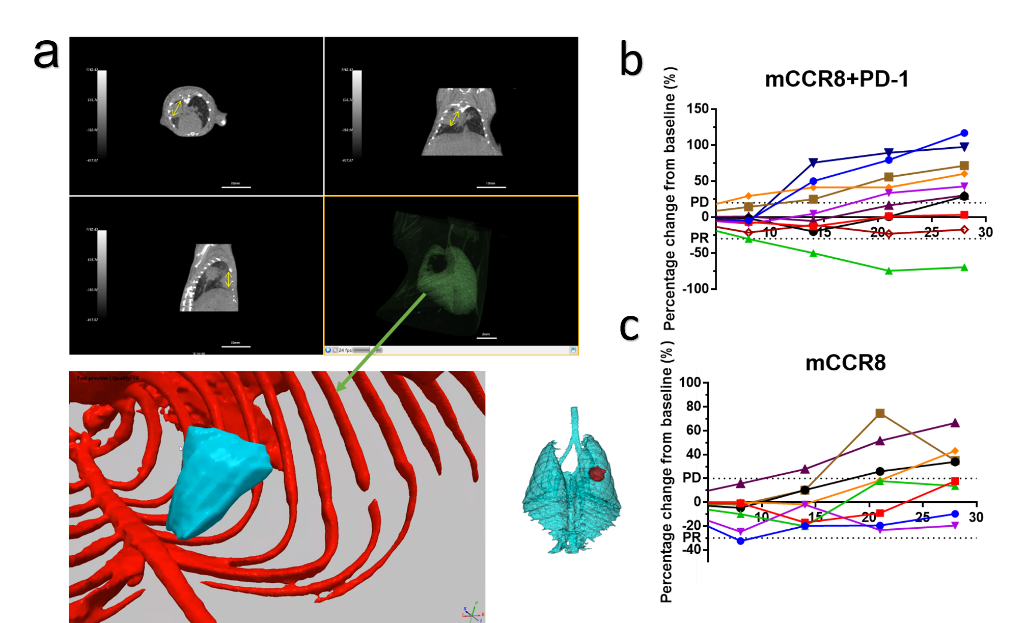

肺部原位/自发肿瘤小鼠模型 (In vivo)-体积量化评价

FVB老龄鼠自发肺癌抗体药物药效评价。 (a) FVB老年鼠自发肺癌结节示意图,分别展示了横断面、冠状面、矢状面以及三种不同渲染方式的3D重建图像(绿色:肺部,红色:骨骼,蓝色:肿瘤,来自软件“simpleware”,蓝色肺部和红色肿瘤)。(b,c) 单臂试验下,靶向药物治疗后结节抓取绘制3D重建图像,其体积的变化量统计图。(n=每组10/8)